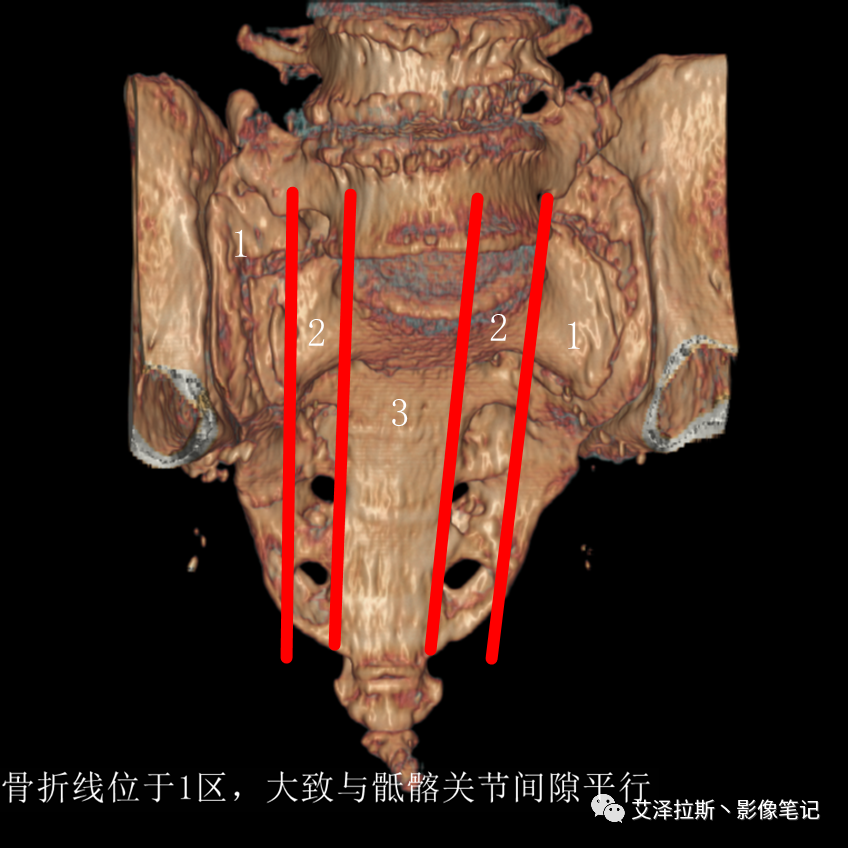

①单侧或者双侧骶骨翼骨折,典型者呈“H”形,即“Honda征”;

②骨折线位于骶孔外侧(如下图,主要发生于1区),通常可能会伴随耻骨的功能不全骨折(如:病例2 右侧耻骨上支骨折,L5双侧横突骨折);